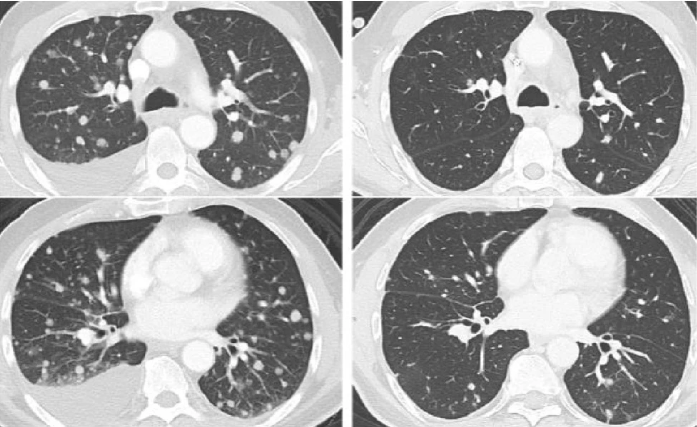

在过去的几年中,细胞免疫疗法为癌症治疗提供了一种新的策略。最近的临床研究表明,肿瘤浸润淋巴细胞(TIL)治疗在晚期实体瘤的治疗中显示出良好的疗效,这为癌症患者带来了新的希望。

近年来,癌症治疗领域迎来了一场革命性的变化。从传统的手术、化疗和放疗到靶向治疗和免疫治疗,科学技术的进步不断重塑着癌症治疗的模式。其中,细胞免疫治疗作为有前途的方向之一,受到越来越多的关注。在各种细胞免疫疗法中,肿瘤浸润淋巴细胞(TIL)疗法近年来尤为突出,甚至在一些晚期癌症患者中取得了惊人的“临床治愈”效果。

在过去的几年时间里,细胞免疫疗法已经逐步成为了癌症治疗的有力策略。其中,肿瘤浸润淋巴细胞(TIL)疗法在实体瘤治疗中的临床应用显示出良好的疗效。